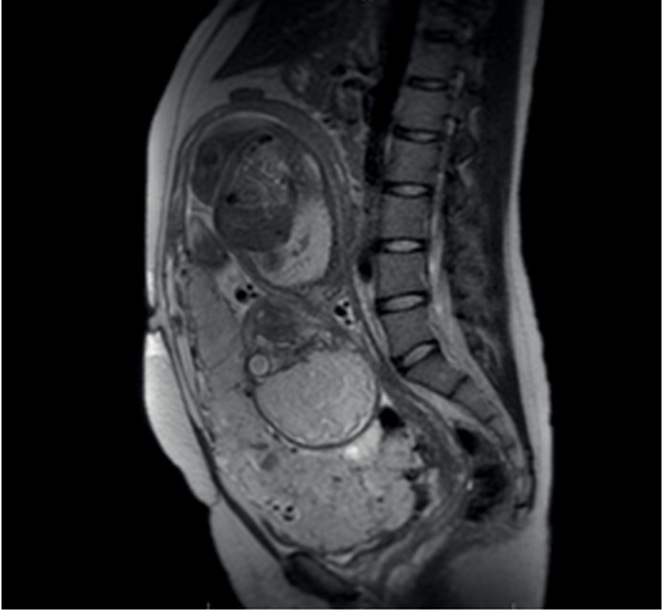

Posteriormente, se realiza la confirmación de la sospecha diagnóstica ecográfica mediante resonancia magnética (figura 4). Existía, además, la sospecha imagenológica de invasión hacia la vejiga, por lo que se consideró pertinente el traslado al Hospital de Clínicas para completar valoración por equipo multidisciplinario especializado.

Queda claro por todo lo expuesto la importancia del diagnóstico prenatal, el cual desempeña un papel esencial en el manejo de pacientes con acretismo placentario. En nuestra paciente la sospecha ecográfica oportuna de acretismo placentario, posteriormente reafirmada por resonancia magnética a las 31 semanas, permitió la correcta planificación y preparación multidisciplinaria donde participaron los equipos de ecografía, urología, anestesia, imagenología, hemoterapia, neonatología y salud mental.